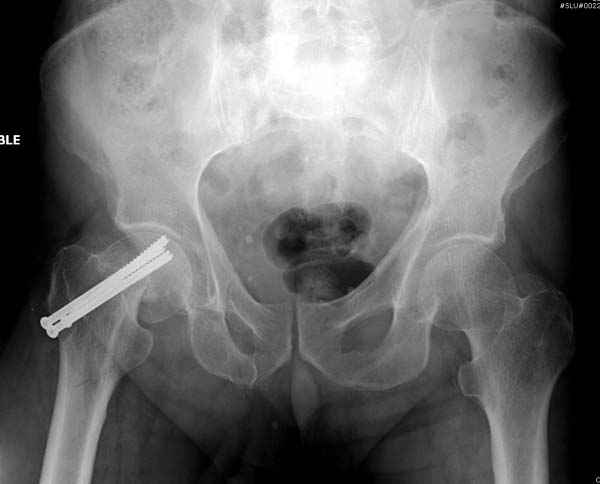

На второй день после выписки упал дома. Снимки приложены. Коллеги рекомендуют удаление шурупа и вытяжение. Что делать?

Привет из солнечного Будапешта с Eurotrauma-2008. Да, замечательный пример. Получается, профилактику расхождения отломков шейки надо было проводить каким-то реконструкционным или проксимальным гвоздем, причем сразу длинной версией. Сейчас, наверно, так и надо бы сделать.

Убрать винты, каким-то джойстиком в вертельной области сделать репозицию шейки, фиксировать ее спицами, а дальше вправлять и фиксировать как вертельный перелом.

Решайте проблемы по мере поступления. На первом этапе решение одно, и на мой взгляд верное. Ситуация изменилась кардинально - другое решение. Я бы избрал ресинтез, убрав винты заменил на Гамму. Что с ним будет послезавтра? - Будем решать послезавтра. Такая наша доля.

Правильно, ситуация изменилась, как говорят у нас теперь "different animal", надо решать проблему подвертельного перелома. При наличии различных вариантов фиксаторов, включая Страйкер Гамма 3, мы выбрали DePuy Antegrade Trachanteric Nail из-за многовариантности проксимальной фиксации и двойного изгиба. Вводится через вертел под 8 градусным углом, и есть достаточный передний диафизарный изгиб, предупреждающий пенетрацию дистального переднего кортекса.

Но ведь и головка бедра сползла в варус - отчего ограничились только фиксацией подвертельного перелома, а не убрали винты и не сделали репозицию шейки?